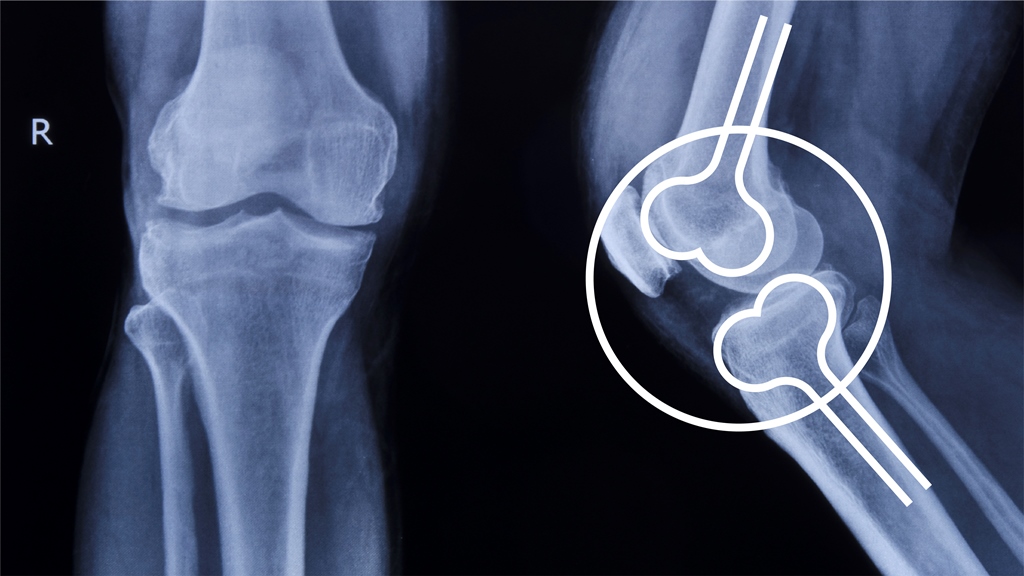

María del Pilar, es una Ortopedista muy especial, ya que su especialidad es la Ortopedia y traumatología en niños, una actividad que le permitió soñar con independizarse y crear su imagen, el desafío era construir su marca con los ingredientes que más la representan: energía, amor y cuidado con el que asume su formación. Este es el desarrollo de su marca.